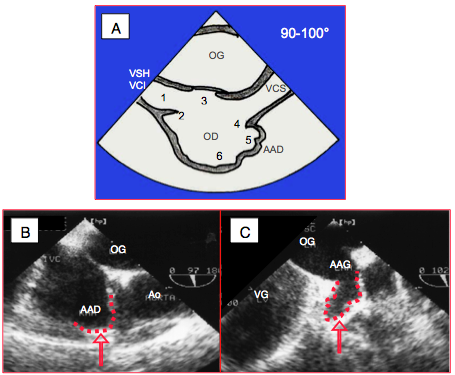

Figure 27.129 : Critères anatomiques définissant l’OD. A: en vue bi-cave 100°. 1 : veine cave inférieure (VCI) ; à défaut de VCI, ce sont les veines sus-hépatiques (VSH) qui se drainent dans l’OD. 2 : membrane d’Eustache. 3 : fosse ovale. 4 : crista terminalis. 5 : appendice auriculaire, large et obtus. 6 : partie trabéculée. Il est capital de déterminer quelle oreillette est l’OD parce que ceci permet de définir le situs. B: appendice auriculaire droit (AAD) en vue bicave. C: appendice auriculaire gauche (AAG) en vue 2-cavités.